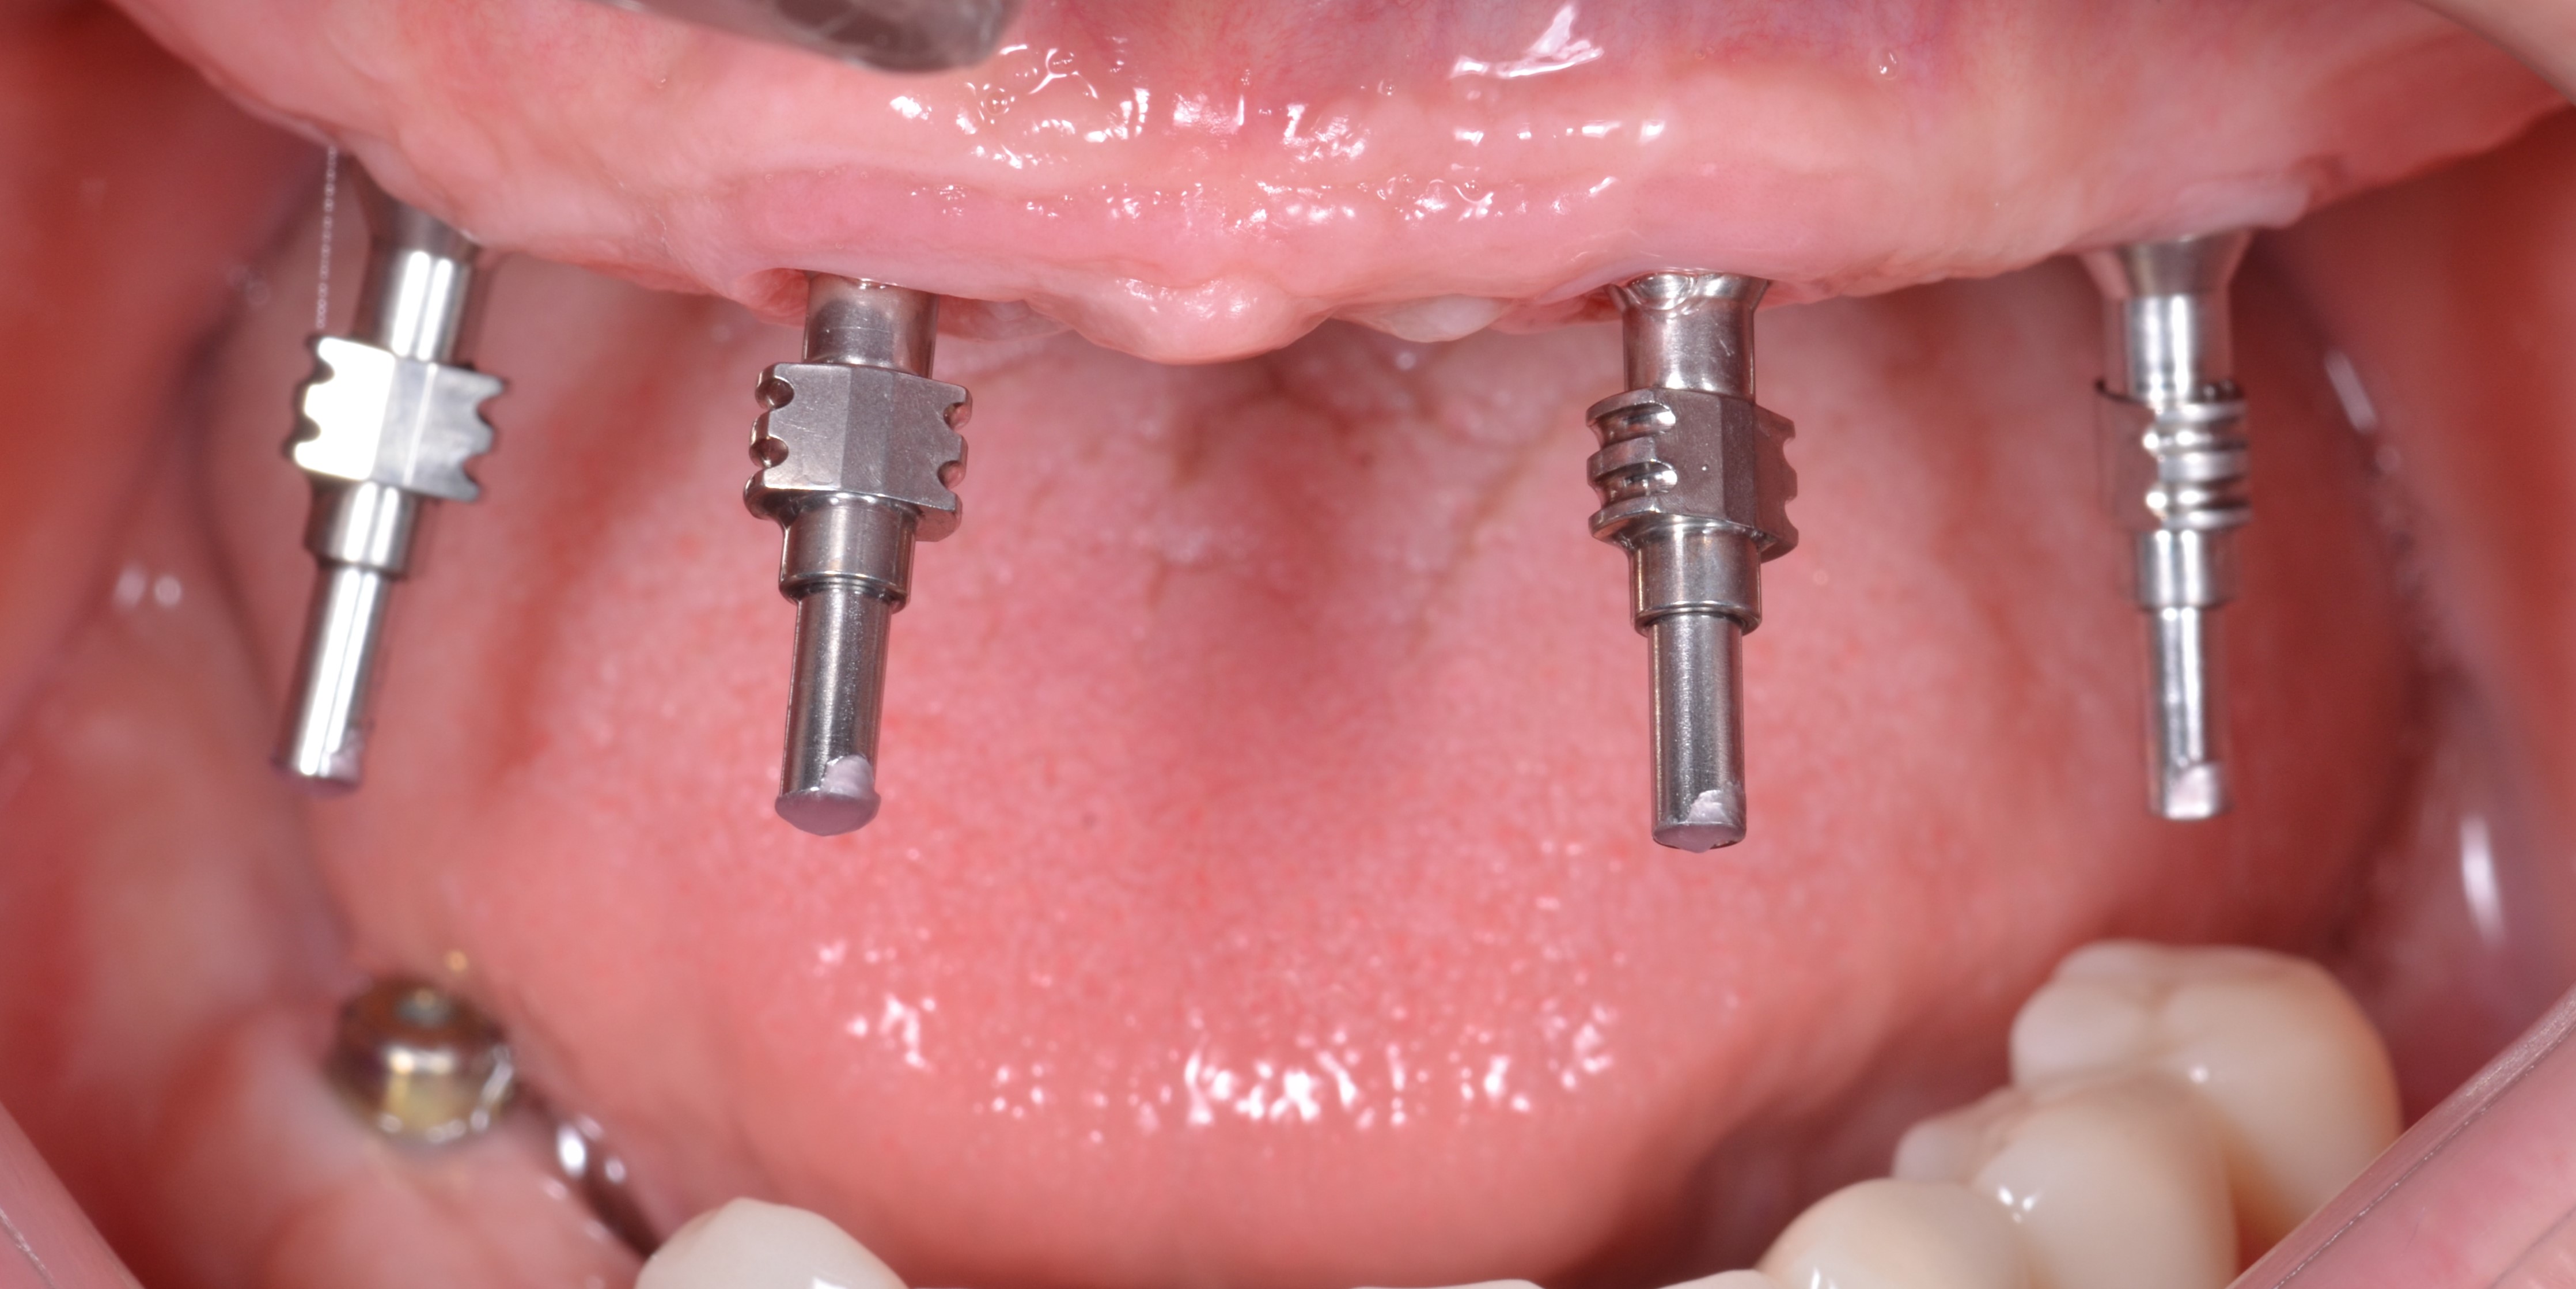

На имплантаты были установлены абатменты для винтовой фиксации «Multi – unit»: в боковых участках угловые 30О абатменты , во фронтальных участках – прямые абатменты (рис. 20,21)

Временные титановые цилиндры были зафиксированы к абатментам «Multi – unit» (рис. 31).